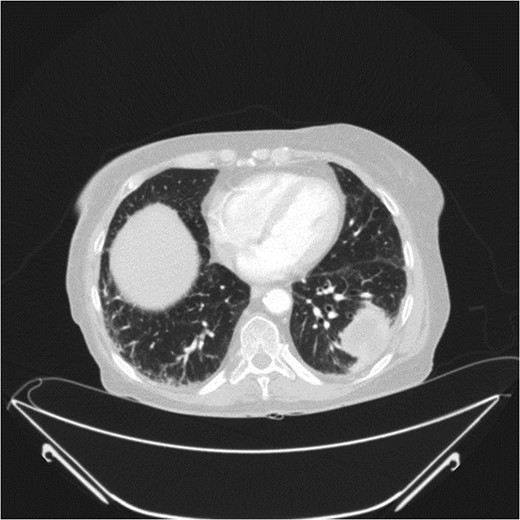

At presentation her vital signs were stable. Abdominal exam revealed exquisite tenderness in the right lower quadrant, with no evidence of digital clubbing. Blood-work revealed an elevated WBC of 15.6. A CT scan demonstrated a 4.3 cm annular mass within the cecum, suspicious for a primary colonic malignancy, as well as an 8.6 × 8.2 cm2 lobulated gas-containing abscess with extension in to the lateral abdominal wall (Figs 4 and 5).

Abdominal CT scan showing annular cecal mass with evidence of perforation.